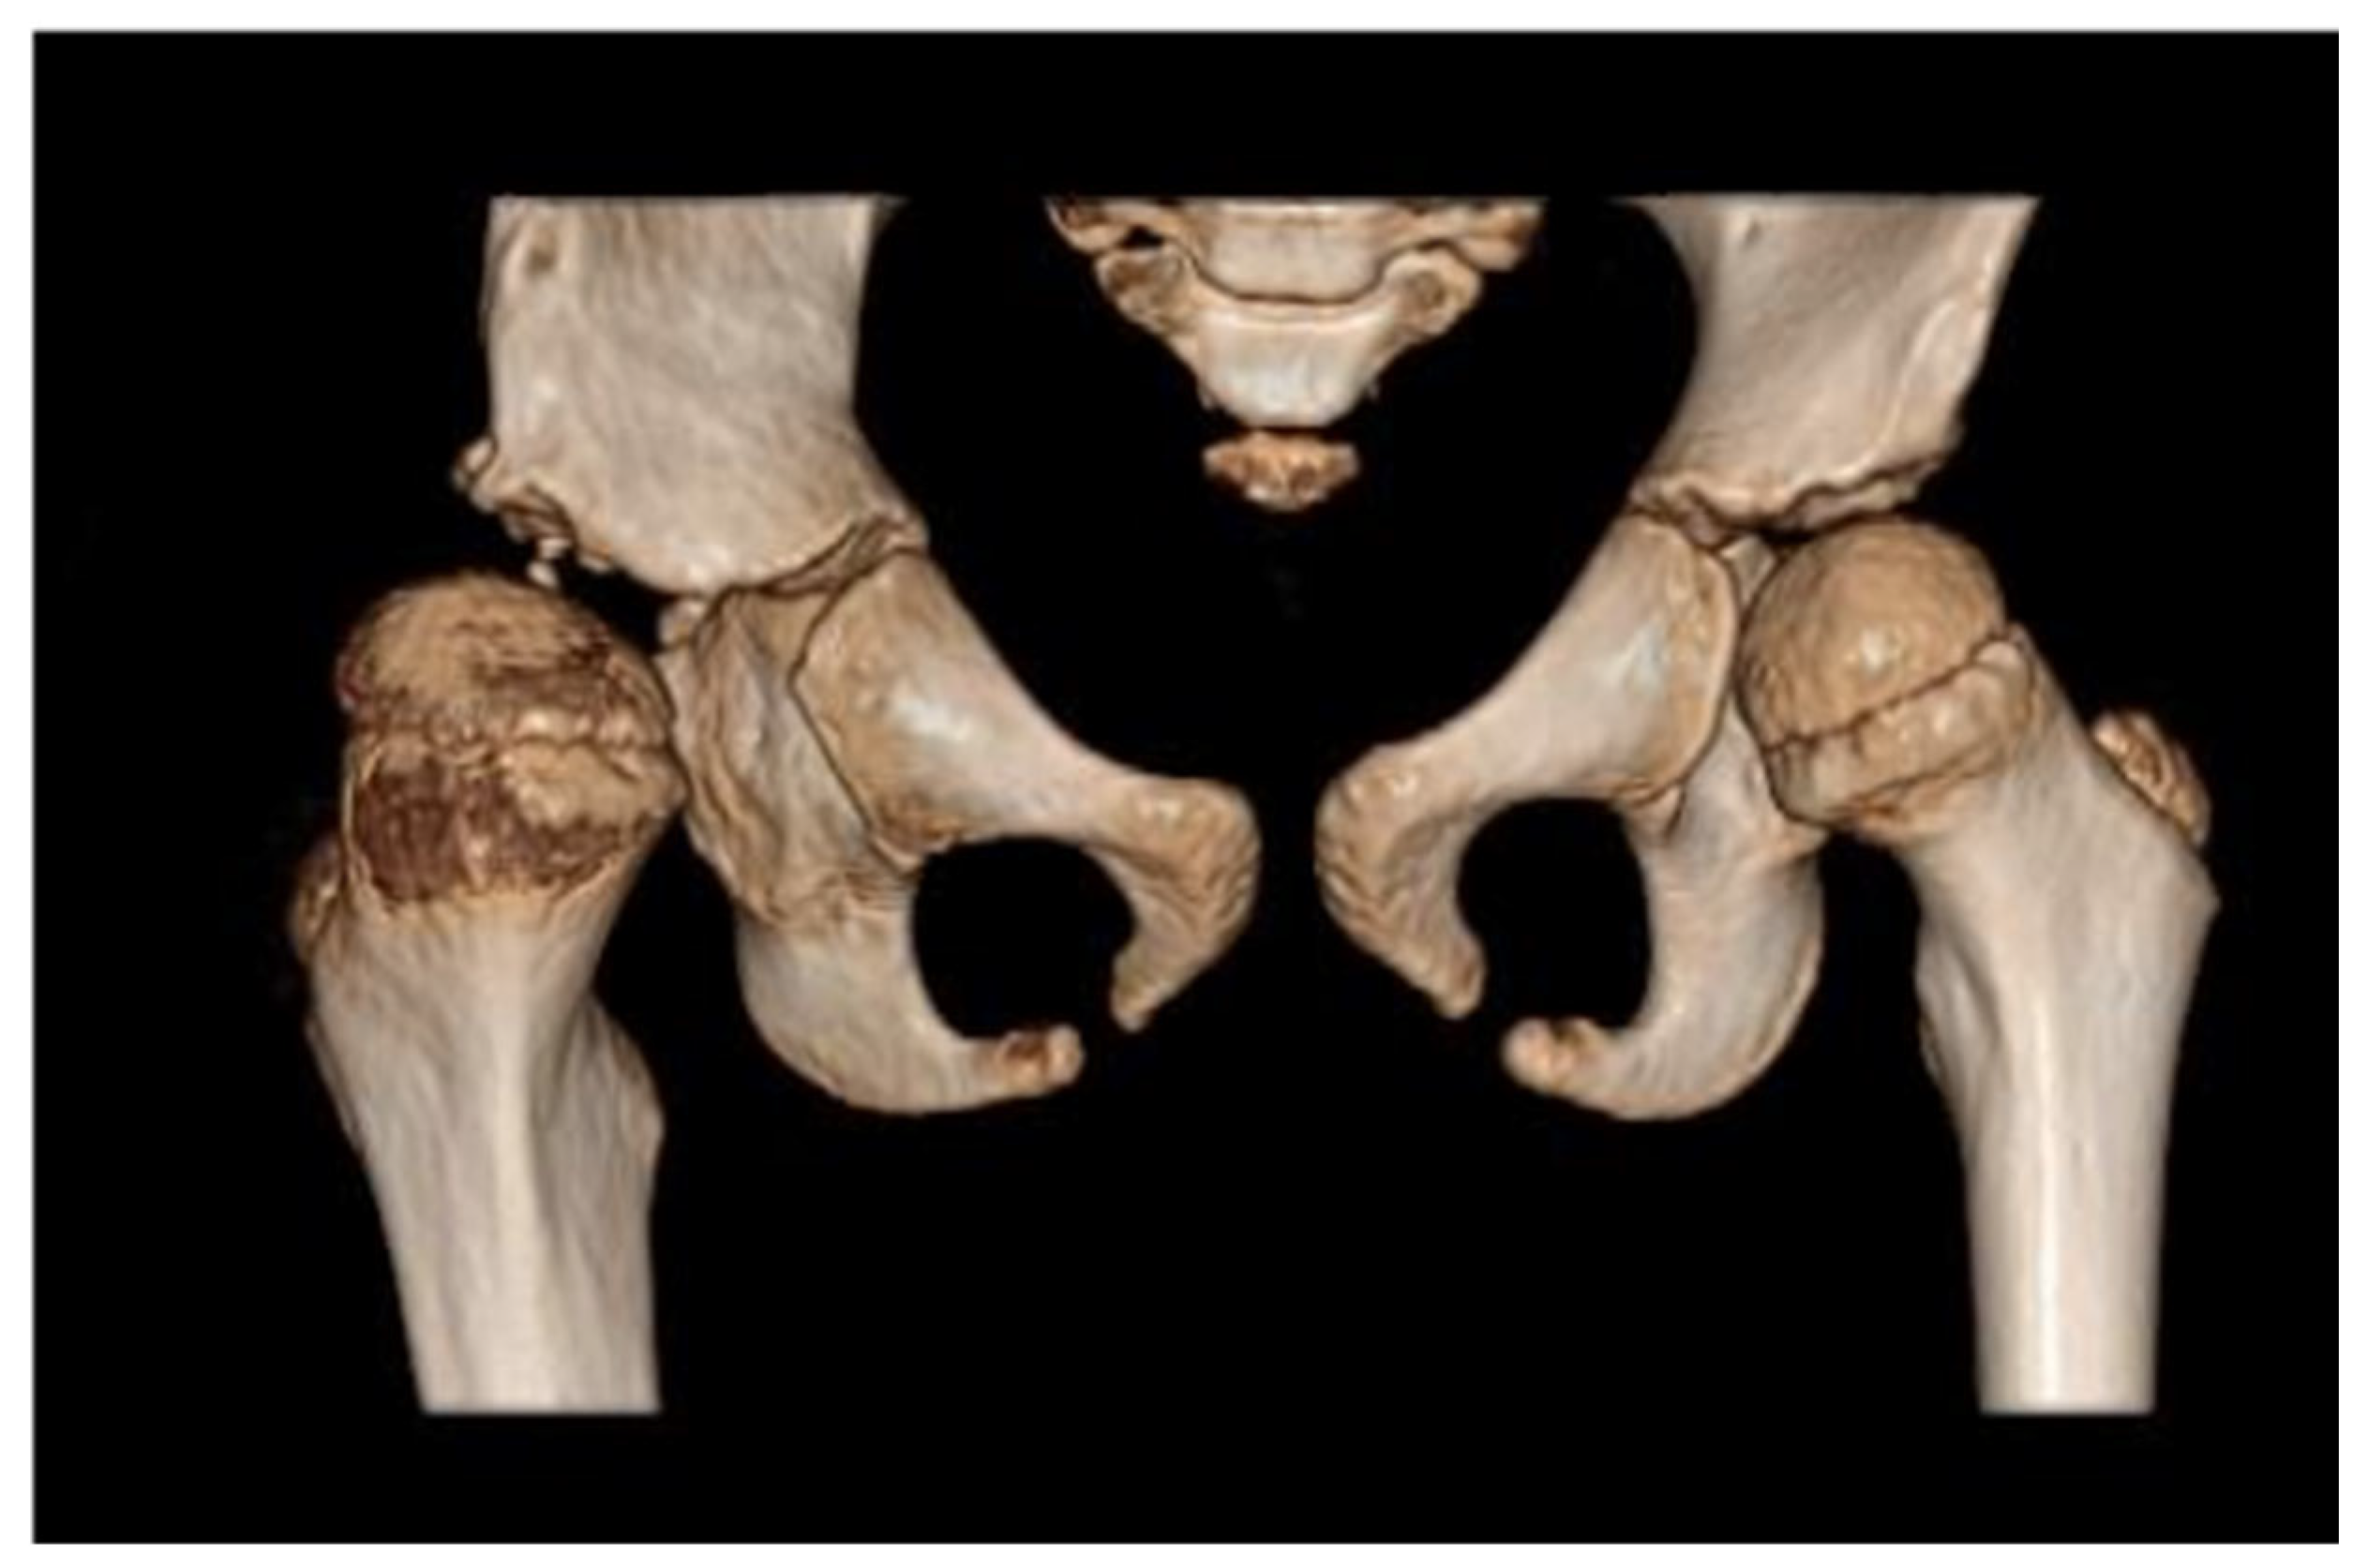

Due to persistent radiological evidence of subluxation in the right hip joint, at the age of 4.5, another pelvis osteotomy was performed using the Salter method. At the age of five, all metallic osteosyntheses were surgically removed and a pelvic computed tomography (CT) scan was performed (Figure 4). The next (third) surgery involving varus direction and de-rotative osteotomy on the proximal part of the right femur was performed on the girl at age 6 (Figure 5).

Figure 4. Computed tomography (CT) of the pelvis—3D scan carried out at 5 years of age. The relative tilt angle of the femoral head is about 47°; the angle of internal rotation is about 25°. Knee set in internal rotation. Femoral head in anterolateral subluxation. Joint space significantly widened. Thickening of soft tissues around the hip joint; exudate cannot be excluded. Differentiation reveals postoperative changes and inflammation. The acetabulum is slightly distorted in the area of the roof and flattened with irregular contours, marginal sclerotization, and small defects. A ~4 mm calcification or ossification can be seen in the soft tissues in front of the anterior part of the acetabular roof and below the posterior edge of the roof. The femoral head is flattened. There is marked thinning of the bone structure of the femoral head and neck.